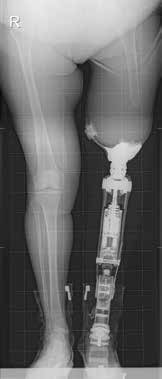

Bei der Durchführung des Indikationsverfahrens wird von den Autoren ein multidisziplinärer Teamansatz verfolgt. Das Behandlungsteam für die Osseointegration besteht aus einem orthopädischen Chirurgen, einem Fallmanager, einem Rehabilitationsmediziner und einem Physiotherapeuten. Patienten, die zur Implantation einer knochenverankerten Prothese überwiesen werden, werden vom Fallmanager in eine ambulante Gruppenklinik eingeladen. Vor ihrem Besuch füllen sie den Fragebogen für Personen mit einer transfemoralen Amputation (Q‑TFA) aus 1. In der ambulanten Gruppenklinik wird zunächst eine radiologische Untersuchung des verbleibenden Femurs bzw. der verbleibenden Tibia durchgeführt und eine kalibrierte Gesamtansicht der beiden unteren Extremitäten angefertigt (Abb. 1a). Bei Patienten mit Unterschenkelamputation oder mit kurzem Oberschenkelstumpf wird ein CT-Scan durchgeführt. Mit diesem CT-Scan werden die Größe und das Design des anzufertigenden kundenspezifischen Implantats ermittelt. Sämtliche Einzelheiten der Behandlung werden im Rahmen einer Plenarsitzung vom Chirurgen und vom Rehabilitationsmediziner vorgestellt, gefolgt von Einzelberatungen mit dem gesamten Osseointegrationsteam. Während der Einzelgespräche werden dem Rest der Kandidaten und ihren Angehörigen zwei Personen mit knochenverankerter Prothese vorgestellt, die ihre Rehabilitation erfolgreich abgeschlossen haben. Diese berichten den neuen Kandidaten von ihren Erfahrungen und zeigen ihnen ihre knochenverankerte Prothese. Abschließend wird ein gemeinsamer Konsens in Bezug auf die Indikation zur Behandlung auf Grundlage der Ein- und Ausschlusskriterien 2, der Krankengeschichte, der körperlichen Untersuchung, der Q‑TFA-Ergebnisse sowie der Radiographie erzielt. Kandidaten mit unrealistischen Erwartungen an ihre zukünftige Funktionsfähigkeit mit einer knochenverankerten Prothese werden an die klinischen Psychologen zum Gespräch überwiesen, um ihre Erwartungen zu korrigieren, die wahrscheinlich zu hoch sind.

Als die Autoren 2009 in den Niederlanden das auf die Osseointegration bei Amputierten spezialisierte Zentrum gründeten, gab es viele Diskussionen und Zweifel bei Ärzten und Orthopädie-Technikern bezüglich der Sicherheit knochenverankerter Prothesen (Abb. 1b). Zweifel bestanden insbesondere im Hinblick auf das mögliche Risiko bezüglich septischer Lockerung, Osteitis und Osteomyelitis. Dies hat das Autorenteam dazu bewogen, eine restriktive Politik bezüglich der Einschluss- und Ausschlusskriterien 3 anzuwenden und die postoperativen Ergebnisse hinsichtlich Sicherheit und Leistungsfähigkeit sorgfältig auszuwerten. Sie gingen davon aus, dass die Anwendung strenger Einschluss- und Ausschlusskriterien zum besten Verhältnis von Sicherheit und Leistungsfähigkeit führen würde. In einer ersten Studie veröffentlichten die Autoren 2016 gemeinsam mit der OGAAP (Osseointegration Group of Australia Accelerated Protocol) die Ergebnisse der ersten 86 Patienten mit zweijährigem Follow-up. Die Studie umfasste 86 Patienten und bestätigte die Sicherheit der Behandlung mit knochenverankerten Prothesen. Es traten keine (a)septischen Lockerungen auf, und Patienten berichteten von einer enormen Verbesserung ihrer funktionellen Leistungsfähigkeit und ihrer Lebensqualität 4. Die Knochenqualität des Stumpfes ist kein Ausschlusskriterium für knochenverankerte Prothesen, da in der Regel die meisten Amputierten an mehr oder weniger schwerer Inaktivitätsosteoporose leiden. Bei Oberschenkelamputierten unterstützen Schaftprothesen das Becken und entlasten das Femur, was zu einer Inaktivitätsosteoporose des diaphysären und metaphysären Knochens führt. Für Patienten mit posttraumatischer Knochenverformung werden auf der Grundlage von CT-Scans maßgefertigte Implantate entwickelt.